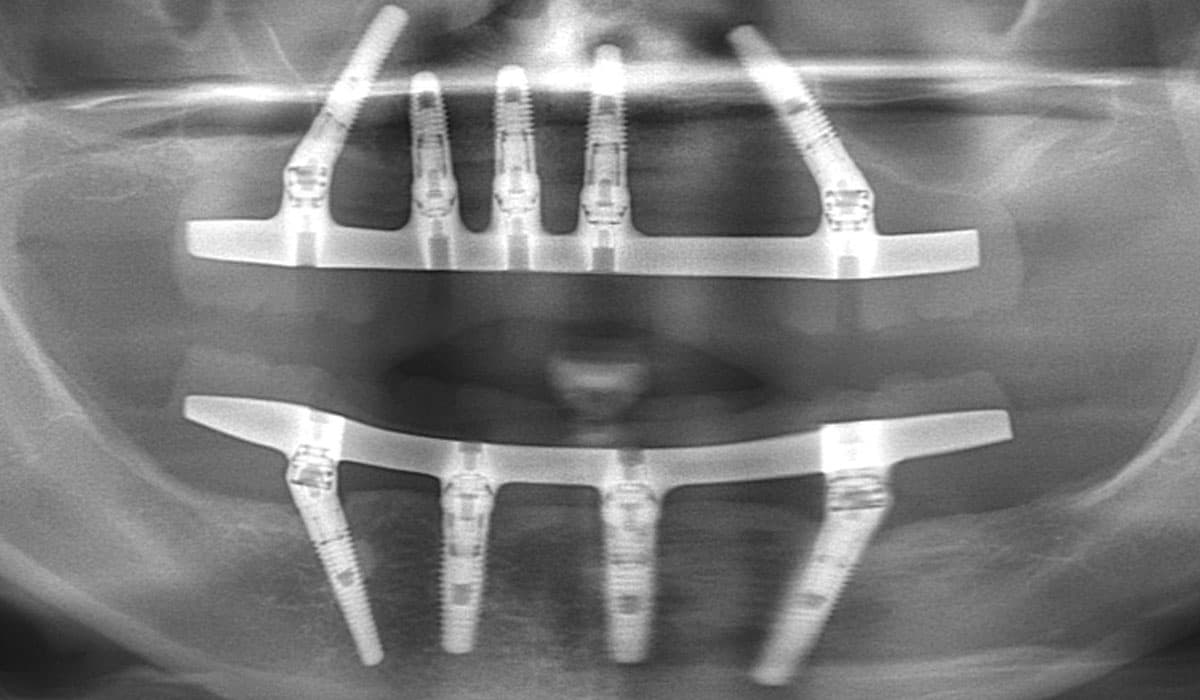

Receive a complete set of permanent teeth in a single visit with our All-on-4 and All-on-6 immediate-load implant protocols. Dr. Antipov uses 3D cone beam CT imaging and computer-guided surgical templates for precise, predictable placement — even for patients who have been told they don't have enough bone. For severe upper jaw bone loss, we offer zygomatic implants anchored to the cheekbone, eliminating the need for extensive bone grafting. Every full arch case includes same-day temporary teeth so you never leave without a smile.

Computer-planned orthognathic surgery to correct jaw misalignment, restore bite function, and achieve facial harmony. Dr. Antipov treats underbites (Class III malocclusion), overbites (Class II malocclusion), open bites, crossbites, facial asymmetry, and obstructive sleep apnea. Procedures include Le Fort I osteotomy (single-piece and 3-piece), bilateral sagittal split osteotomy (BSSO), genioplasty (chin repositioning), maxillomandibular advancement, and double jaw surgery. Every case uses 3D virtual surgical planning for millimeter-precise results.

Computer-Guided Surgery Day

On procedure day, Dr. Antipov uses 3D surgical guides and computer-assisted planning for precise execution. For dental implants, your All-on-4 or All-on-6 implants are placed and same-day temporary teeth attached — all under comfortable IV sedation. For jaw surgery, 3D virtual planning ensures millimeter-accurate repositioning.

3D Computer-Guided Surgery

Every implant and jaw surgery case is planned using advanced 3D cone beam CT imaging and virtual surgical planning software. Computer-guided surgical templates ensure each implant is placed at the precise angle, depth, and position for optimal long-term results. This technology dramatically reduces surgery time and speeds recovery.